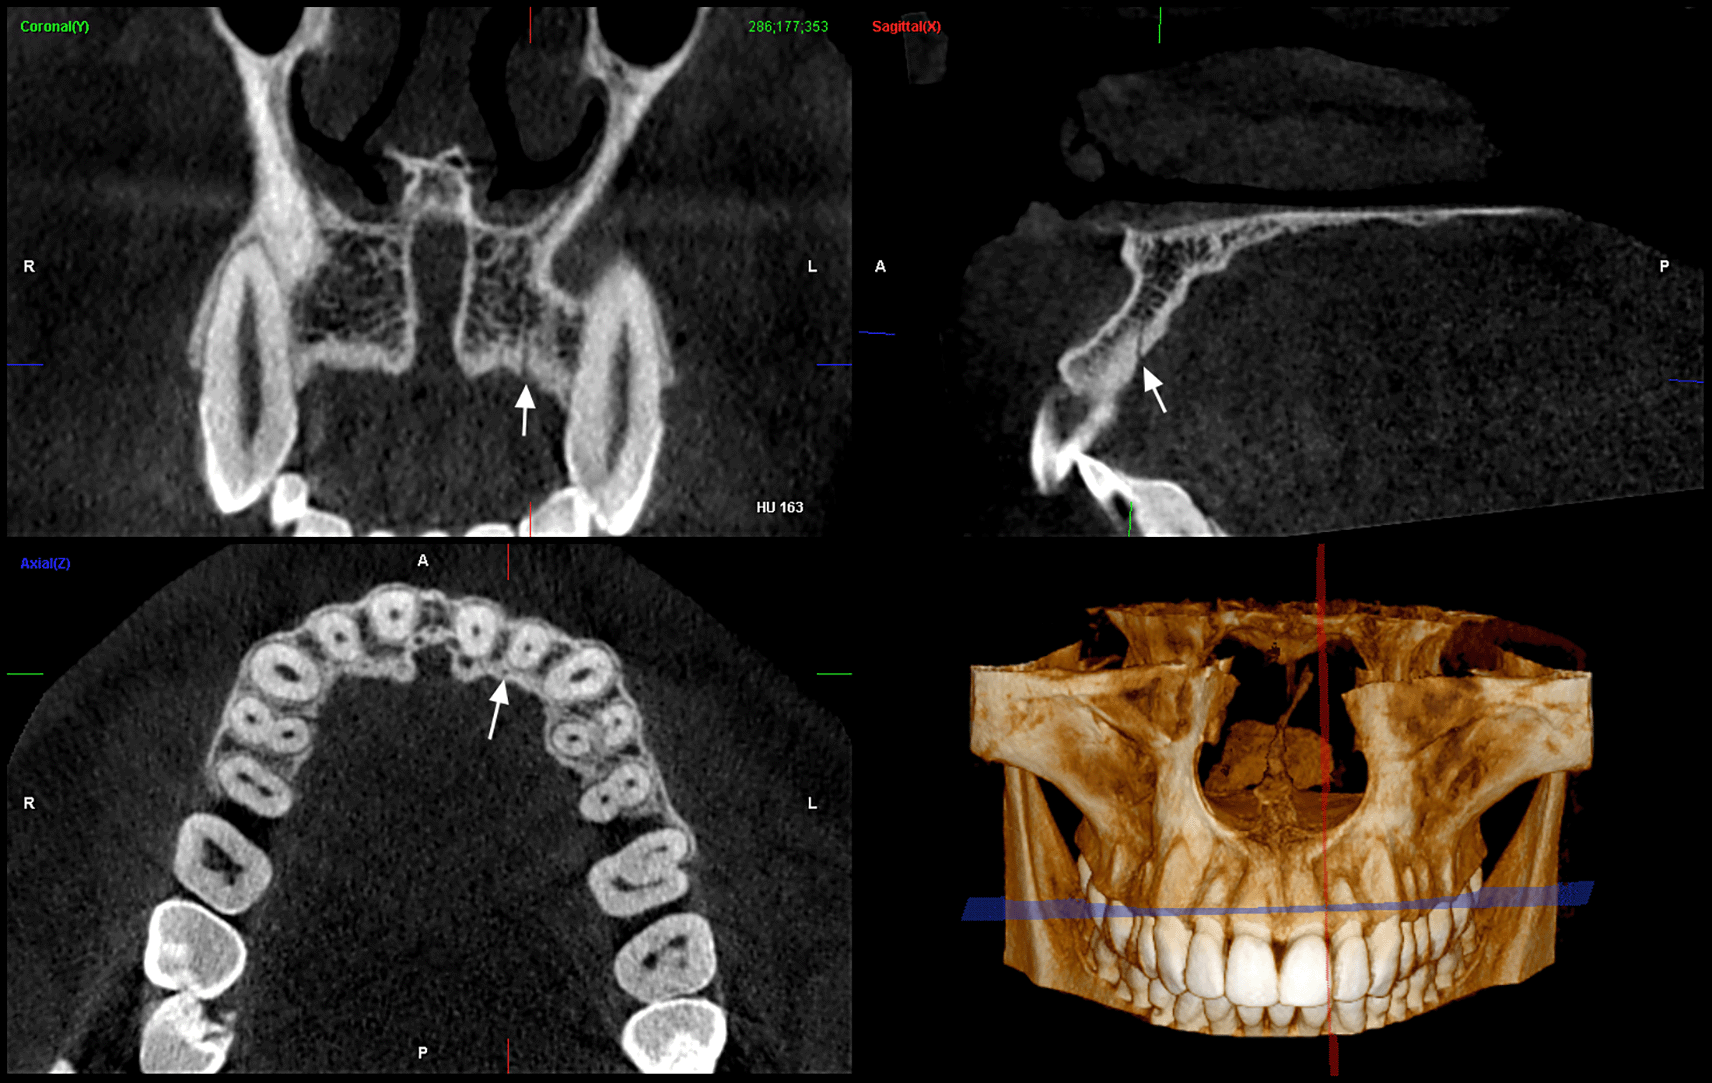

Presence or absence of CS ( Figure 1)

CS position with respect to lateral incisors in different sections ( Figure 2)

Distance of CS from cortical plates, alveolar crest and nasal floor ( Figure 3)

Diameter of the canal ( Figure 4)